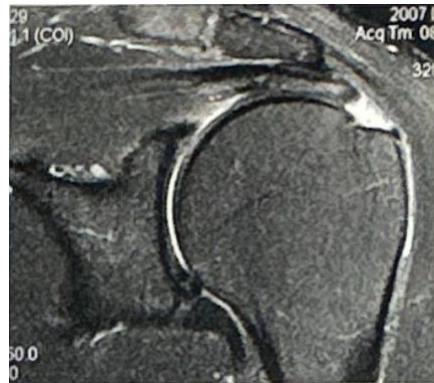

Case: Adhesive Capsulitis (Frozen Shoulder)

Clinical Scenario

- Patient: 55-year-old male, diabetic

- Complaint: Pain and restriction of shoulder movement

Physical Examination Findings:

Assessment Questions

Q1: Describe the physical finding?

- The patient is unable to raise his right hand above his head

Q2: What is your differential diagnosis?

- Adhesive capsulitis (Frozen Shoulder) - Primary diagnosis

- Acromioclavicular arthritis

Q3: What is the treatment for such a case?

- Steroid injection

- Physiotherapy

- Arthroscopic release